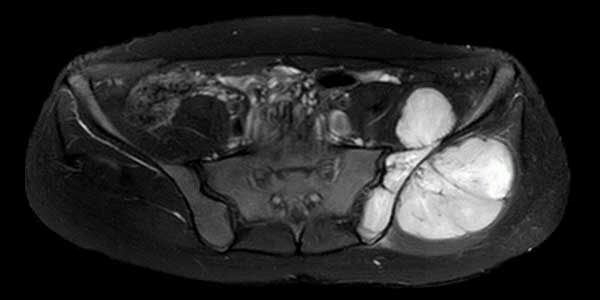

Kondrosarkom - Kıkırdak Doku Kaynaklı Kemiğin Kötü Huylu Tümörü

Kıkırdak doku kaynaklı kemiğin kötü huylu tümörüdür. Sıklıkla 40 yaş sonrası ortaya çıkar. Erkeklerde daha sık görülür. En sık pelvis, kalça ve omuz çevresinde saptanır. Uzun kemiklerin sıklıkla metafiz bölgesinde yerleşir.